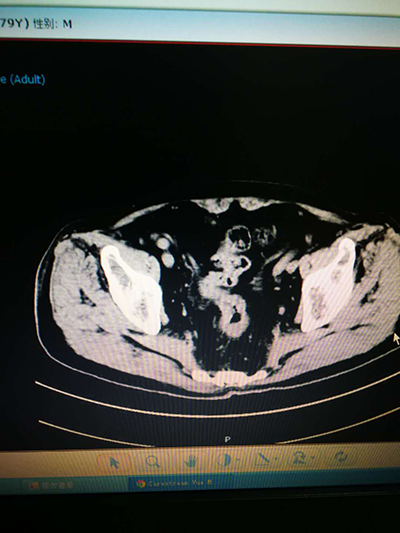

“转化治疗成功”通俗上讲:是指不能手术治疗的晚期恶性肿瘤,经过化放疗等措施使肿瘤降期,能够达到手术治疗标准。患者近三个月前,在我市某三级甲等医院确诊为“直肠癌伴盆腔、肝脏多发转移”,后转入我科,经常规+靶向药物化疗,患者腹泻症状从治疗前近20/日,至目前排便基本正常。此次入院影像检查,患者直肠癌肿缩小,边界清晰,肝脏及盆腔转移肿大淋巴结近消失,符合腹腔镜微创直肠癌手术条件。23日上午,给予患者行“腹腔镜直肠癌Dixon术+预防性末端回肠造口术”。手术历时2个小时,无明显出血,患者术后安返病房。